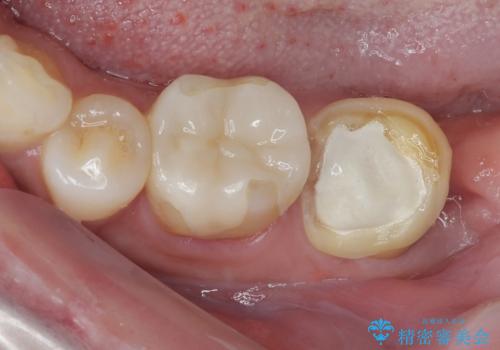

- 他院で「左下の親知らずの手前の歯が虫歯」と診断された患者様の症例です。

診査の結果、下顎左側第二大臼歯の遠心(奥側)に大きな虫歯があり、歯肉の奥深く、骨の縁まで進行している状態でした。

このようなケースでは、虫歯を完全に除去して精密な補綴治療をするのが難しく、長期的な予後が不良となることが多いです。

そこで今回は、抜歯即時インプラントの適応と判断しました。